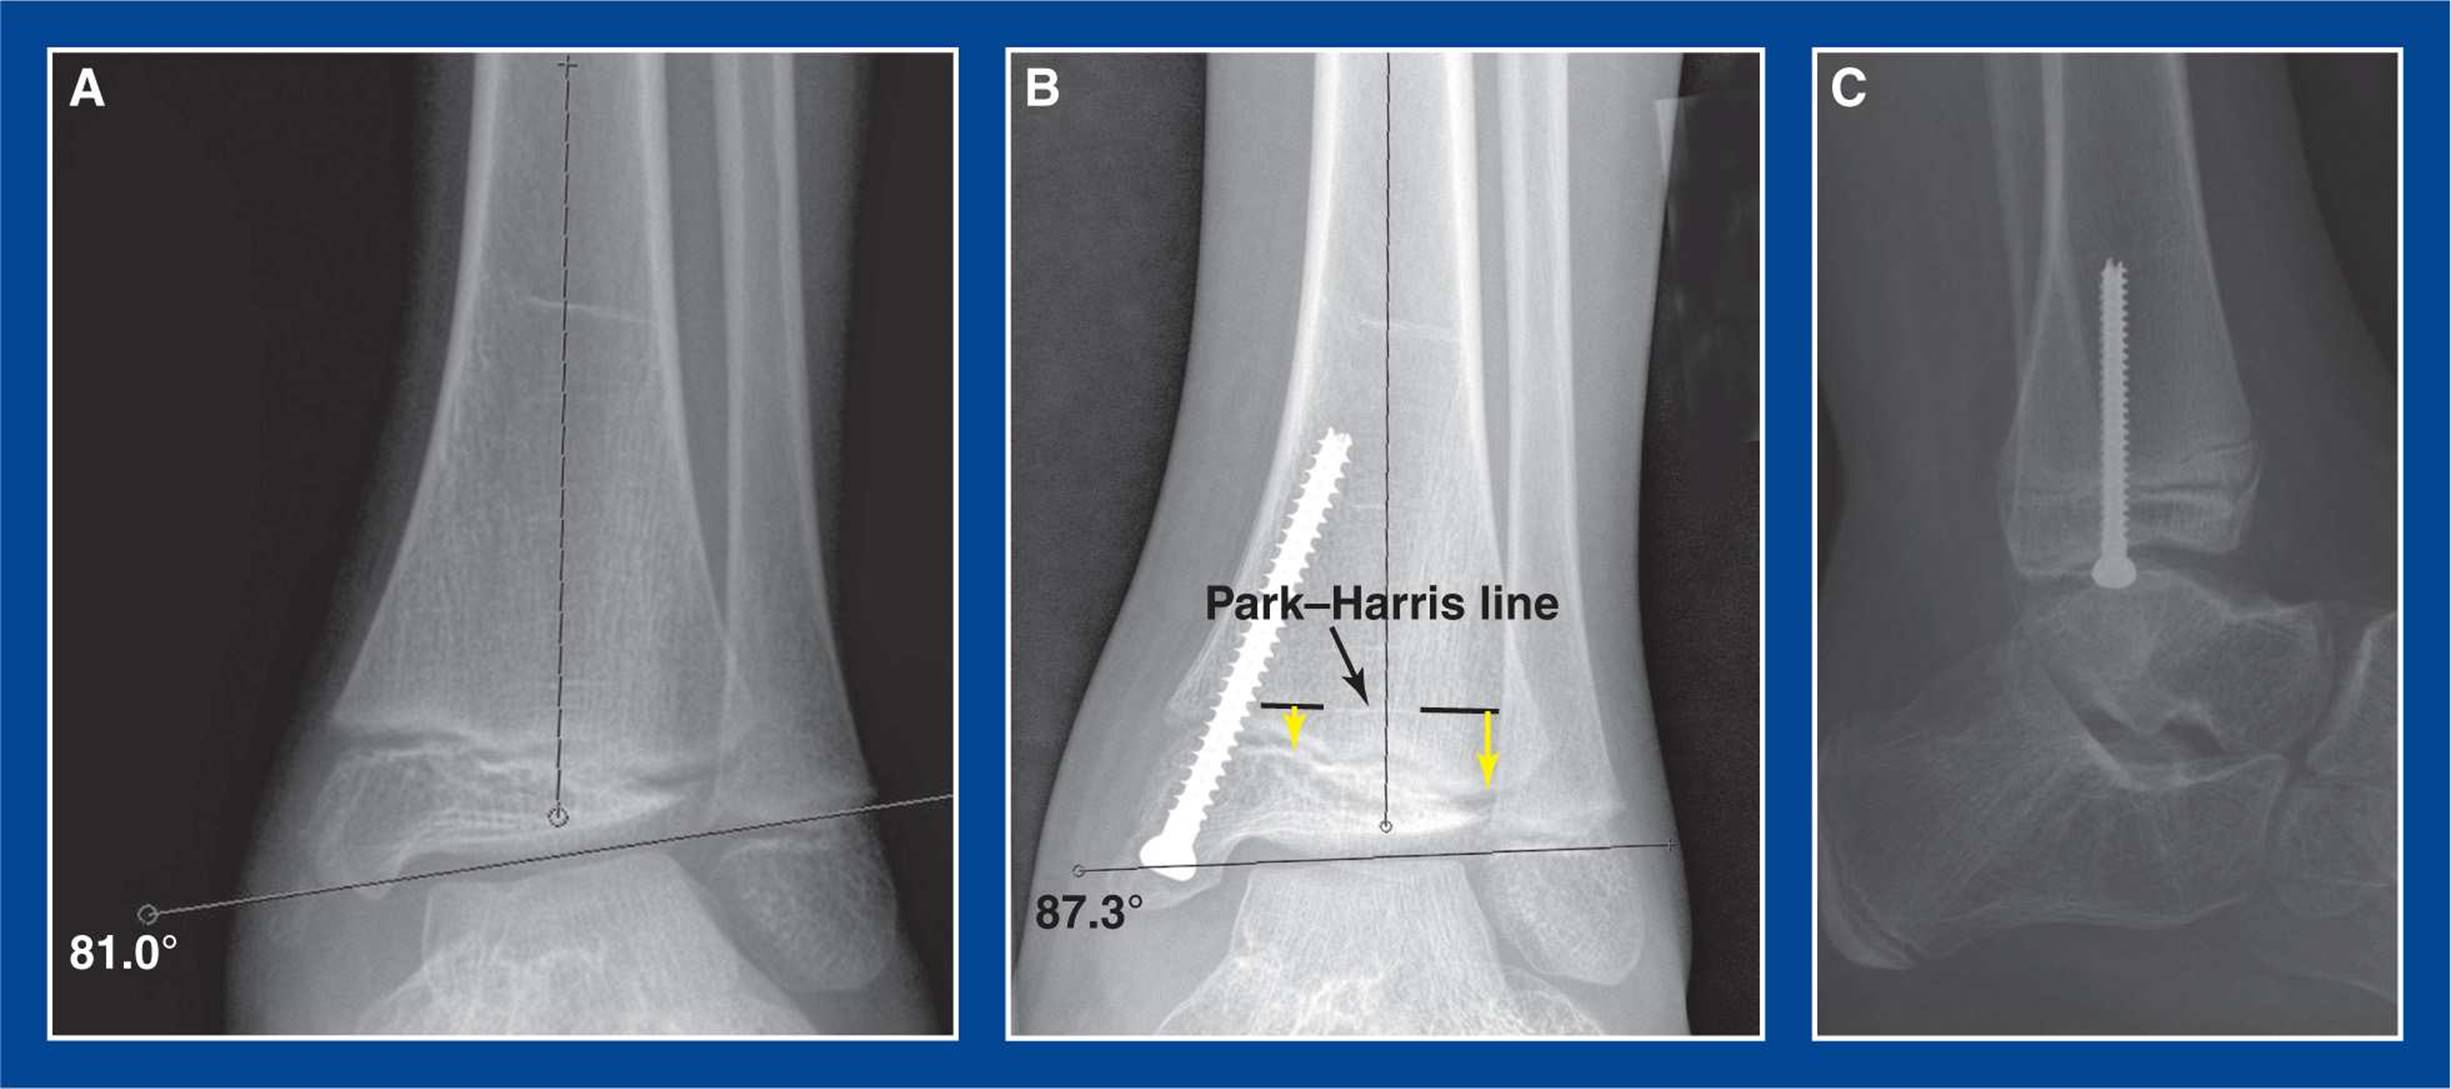

Figure 8-1. Medial malleolus screw hemiepiphysiodesis for guided growth correction of ankle valgus deformity. A. Preoperative AP ankle x-ray showing 9° of valgus deformity. B. 3° of valgus deformity persist 6 months after retrograde insertion of a screw across the medial side of distal tibial physis with a starting point in the center of the medial malleolus. The Park–Harris line (dashed black lines with white P–H line visible between them) confirms deformity correction. The yellow arrows indicate the differential growth of the physis from the P–H line following screw insertion months earlier. C. Lateral radiograph shows that the screw is in the midcoronal plane. This is a true lateral projection of the ankle joint, confirmed by colinear alignment of the posterior cortices of the tibia and fibula at the level of the tibial meta-epiphysis. (see Assessment Principle #20, Chapter 3).